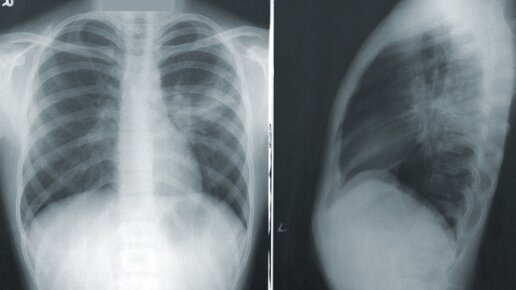

Какие антибиотики назначают при пневмонии

Пневмония - это довольно серьезное заболевание. А это значит, что лечить его самостоятельно ни в коем случае нельзя. Прежде всего нужно обратиться к квалифицированным специалистам, в больницу. Далее нужно будет сдать кровь на анализы и пройти рентген легких...